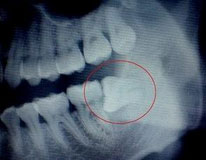

麦芽口腔拥有先进的德国CBCT、全景机,能为您定制合适的拔牙计划。

如阻生智齿等复杂牙,接近下颌神经管、血管,拔牙难度大,对设备精度要求高。